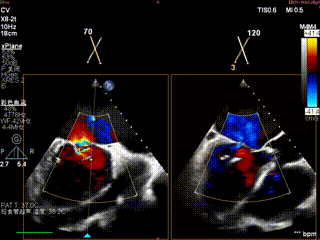

术前TEE评估

术前瓣膜介入团队的心超医生陈星星医师王良国医师对患者的心脏结构和瓣膜解剖情况进行详细的评估:

1.二尖瓣重度关闭不全(4+),瓣环明显扩大(AP径4.6cm,LM径3.9cm),扁平,关闭时瓣叶对合不佳(carpentier I),1-3区均可见反流束,返流宽度达26mm;肺静脉频谱呈收缩期反向。

2.画迹法测得二尖瓣瓣口面积约8.8cm²。

3.PISA法测得EROA=0.57cm²,Rvol=77ml,r=11mm。

4.二尖瓣前叶(A2)长度29mm,后叶(P2)长度11mm。

5.左房巨大(三径86*84*114mm),右房巨大(内径114*86mm),CFI提示极重度三尖瓣反流,Teich法测得EF为70.1%。

1区

1区带彩

2区

2区带彩

3区

3区带彩